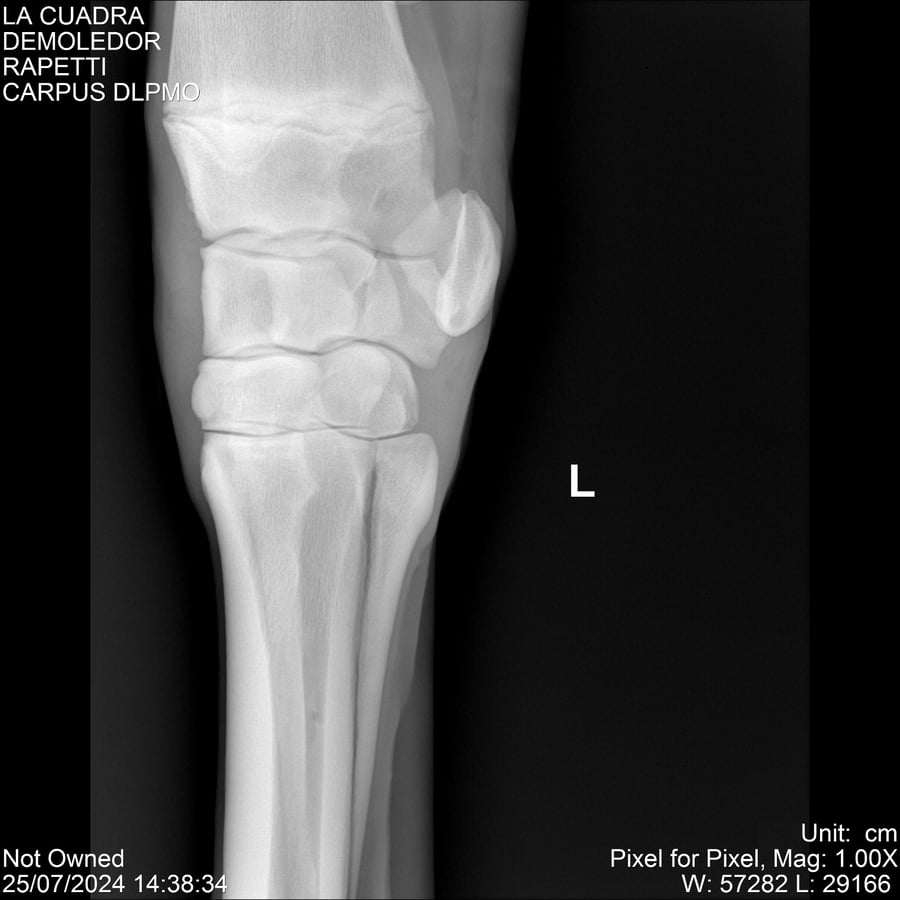

LOTE 14, DEMOLEDOR 🔥 🔥 🔥 Lote Anterior Volver al remate Lote Siguiente Ficha Contacto Montevideo - Ficha del Lote Identificador: #284454 Categoría: Yeguarizos Montevideo - 89 Visualizaciones ClicData Contacto Empresa: Abelenda N. R., Walter Hugo Nombre*: Teléfono* : E-mail* : Mensaje Enviar Registrese gratis Este contenido Exclusivo está disponible sólo para usuarios registrados Ingresar